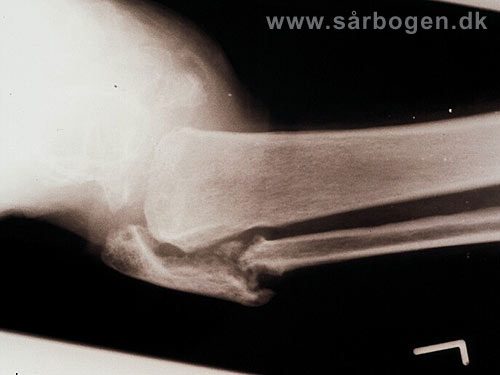

Bøjlebehandling af n...